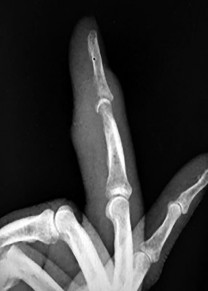

Figures 31a through 31d are the radiographs and MR images of a 52-year-old man who has a 7-week history of right ring finger pain, redness, and swelling. He accidentally stuck his finger with a toothpick 1 week before developing symptoms. There is purulent drainage from the puncture wound site. He was treated with oral antibiotics for 10 days and intravenous (IV) antibiotics for 3 weeks before being seen. Initial cultures grew _Eikenella corrodens_. What is/are the best next step(s)?

This patient had a septic DIP joint that was treated with antibiotics alone. As a result, he developed osteomyelitis with bone destruction and an abscess. The correct answer is debridement of both bone and soft tissue with abscess drainage. Antibiotic treatment without surgery would not successfully eliminate this infection. A bone scan and biopsy are not appropriate because this problem is an infection and not a tumor, and the MR imaging provided enough diagnostic information. Amputation is not indicated prior to an attempt to salvage the digit. Amputation through the DIP joint would not remove the infected bone in the middle phalanx and would provide an inadequate level of resection.